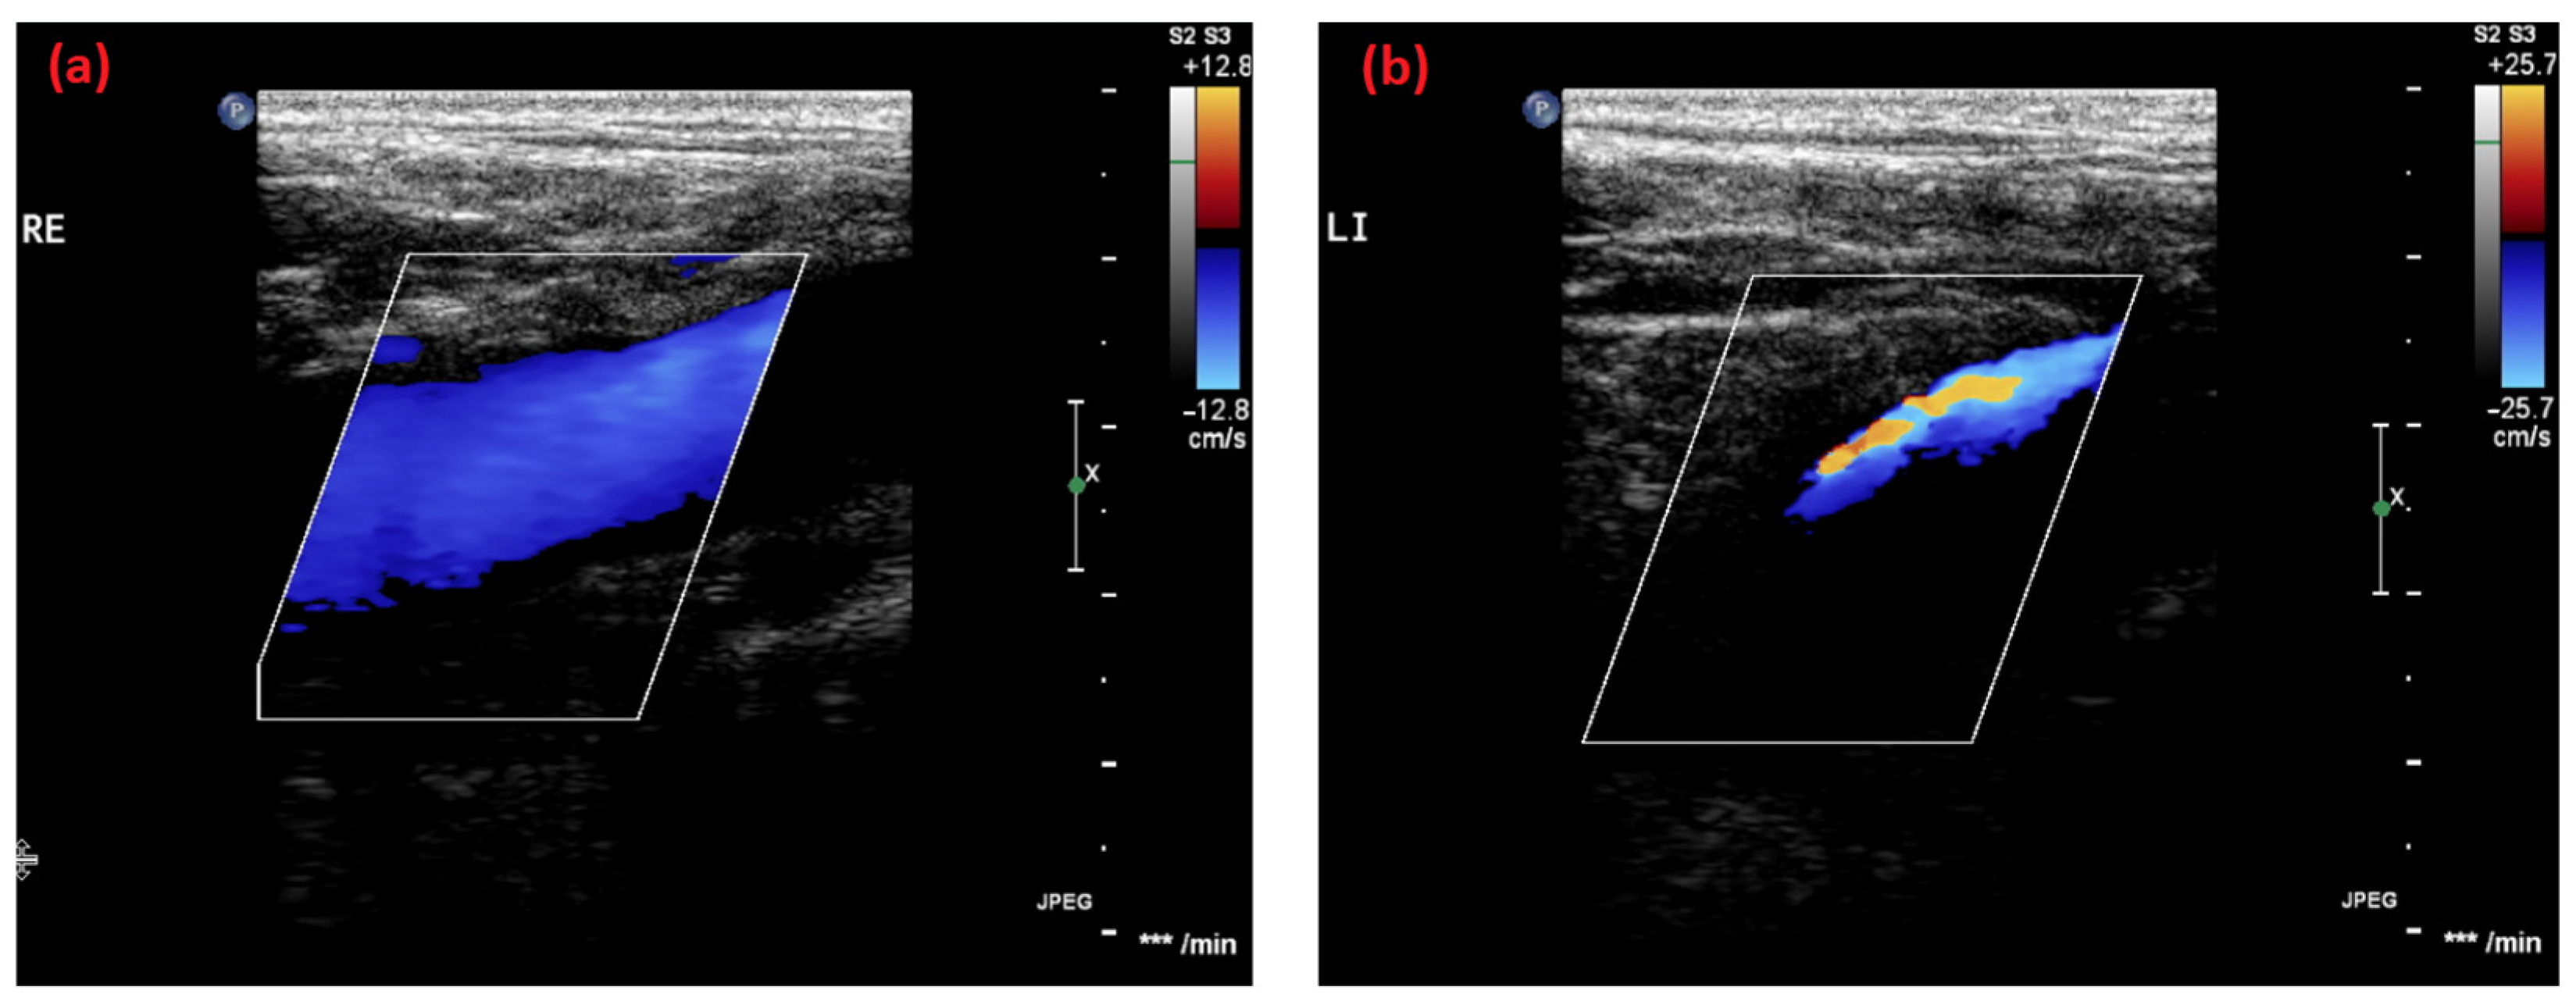

2.1. Case 1

2.2. Case 2

2.3. Case 3